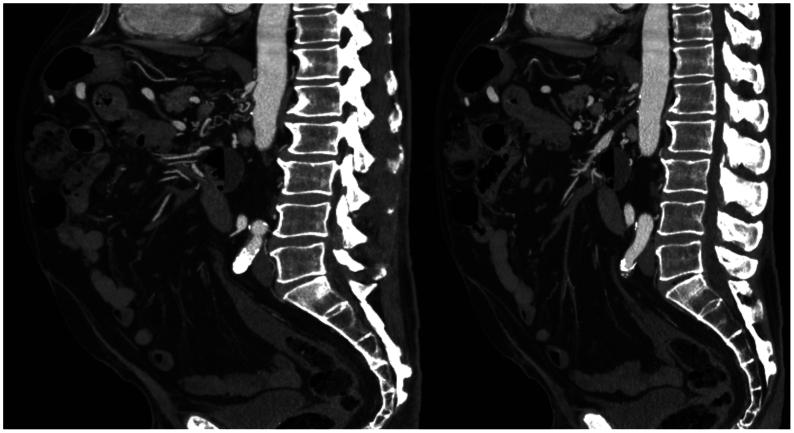

Inferior mesenteric artery (IMA) aneurysms account for approximately 1% of visceral artery aneurysms and can occur secondary to high flow because of occlusive disease in other mesenteric arteries. We describe the case of a 79-year-old man who presented with a 3.3-cm IMA aneurysm and chronic total occlusions of the celiac artery and superior mesenteric artery (SMA). After an unsuccessful attempt at endovascular SMA recanalization, he underwent an uncomplicated retrograde aorta to SMA bypass and antegrade aorta to IMA bypass. We propose that an aorta to IMA bypass after SMA revascularization is safe and effective to treat suspected high-flow IMA aneurysms.